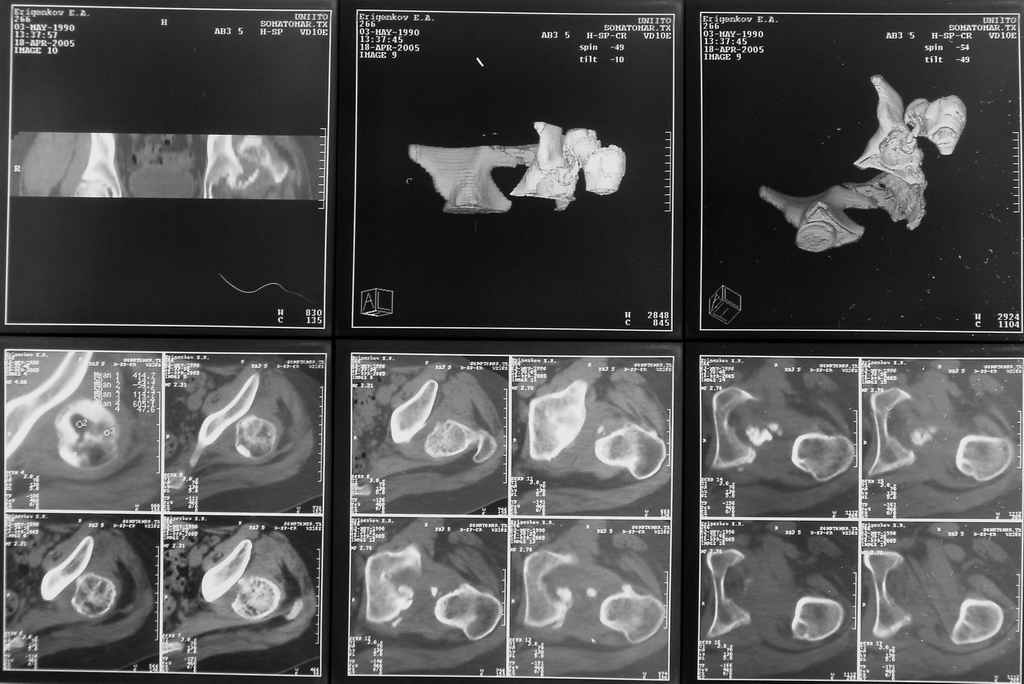

Застарелый вывих бедра (7 мес)

Здравствуйте. К нам поступил мальчик 15 лет с застарелым 7-месячным вывихом бедра из области. Травма мотоциклетная, при поступлении в больницу по месту жительства диагностирован перелом диафиза бедра и не распознан вывих бедра с этой же стороны.

Бедро было синтезировано пластиной и успешно срослось. Как поступить сейчас с вывихом? По КТ видны интерпонированные отломки, впечатление что это фрагменты головки бедра. Поделитесь, пожалуста, опытом. Спасибо.